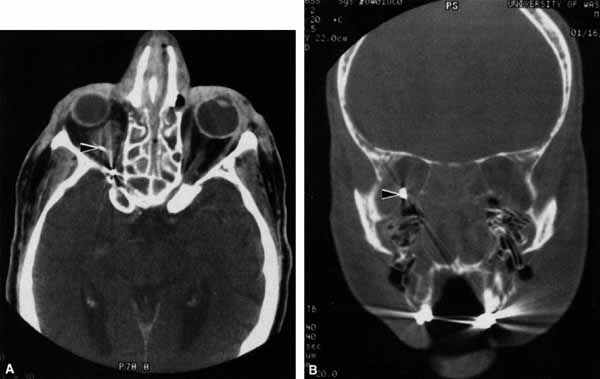

CASE 4

A 52-year-old woman presented with diplopia when looking to her right. She had noted a red right eye for the past 3 months (Fig. 25A). Visual acuity was 20/20 in both eyes and the pupils were normal. The right eye was limited in abduction. Forced duction testing showed abduction of the right eye to be restricted. Intraocular pressures were 23 mm Hg OD, and 15 mm HG OS. CT showed a dilated right superior ophthalmic vein (Fig. 25B) which was shown to be caused by a dural cavernous fistula. The right medial rectus muscle was also enlarged (Fig. 25C) because of blood engorgement, reducing muscle compliance, which accounted for the restricted abduction.

Fig. 25 A. A 52-year-old woman with a right dural cavernous fistula demonstrates a red right eye. B. Computed tomography (CT) scan demonstrates dilated right superior ophthalmic vein (arrow) secondary to the dural cavernous fistula. C. Enlarged right medial rectus muscle (arrow).

Carotid cavernous fistulas can develop either as a result of trauma or spontaneously.47 A direct carotid cavernous fistula results from a tear in the intracavernous carotid artery with arteriolization of the cavernous sinus and superior orbital vein. Concomitant cranial nerve III, IV, VI, V1 and V2 paresis, elevated intraocular pressure, proptosis, and distention of the deep Tenon's vessels anteriorly (see Fig. 25A) with neuroradiologic evidence of an enlarged superior ophthalmic vein are common (see Fig. 25B). Ophthalmoplegia may also occur on a restrictive basis because of engorgement of the extraocular muscles with blood (see Fig. 25C).36 Dural carotid cavernous fistulas occur where small branches of the intracavernous carotid rupture, allowing access of arterial blood to the cavernous sinus. Typically, the findings are similar to a direct carotid cavernous fistula but of less magnitude. There is no history of trauma, and typically occurs in older persons. However, there is crossover between these two types of carotid cavernous fistula. An excessive ocular pulse tonographically may be helpful in the diagnosis of a carotid cavernous fistula in such cases.48